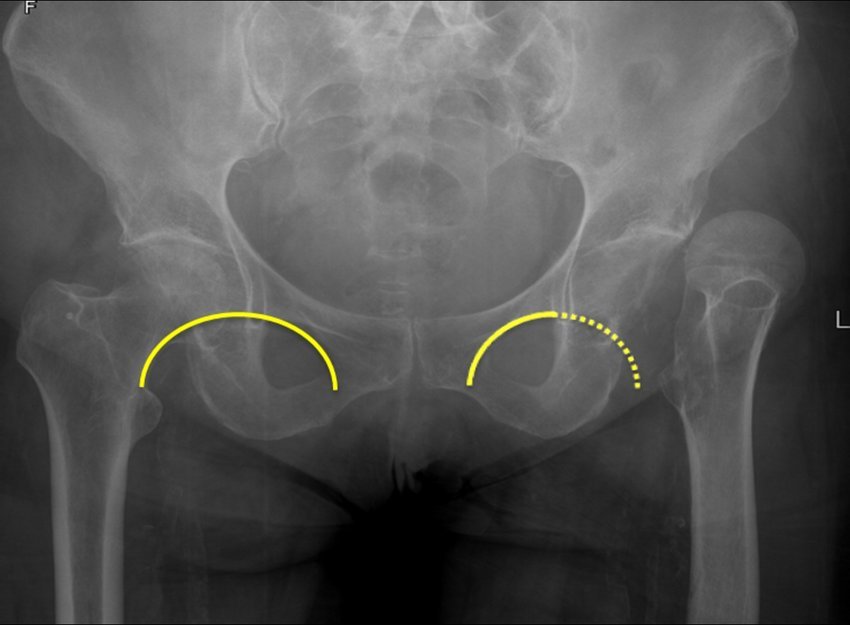

Radiological features: AP views

1) Break in the Shenton’s lines.

2) Prominent lesser trochanter.

3) Look for asymmetry. Compare Shenton’s lines on the AP view. On the lateral view check for angulation of the head in respect to the neck.

4) If suspicious, but no fracture is seen, a bone scan at 48 hours or delayed repeat film can be of benefit.